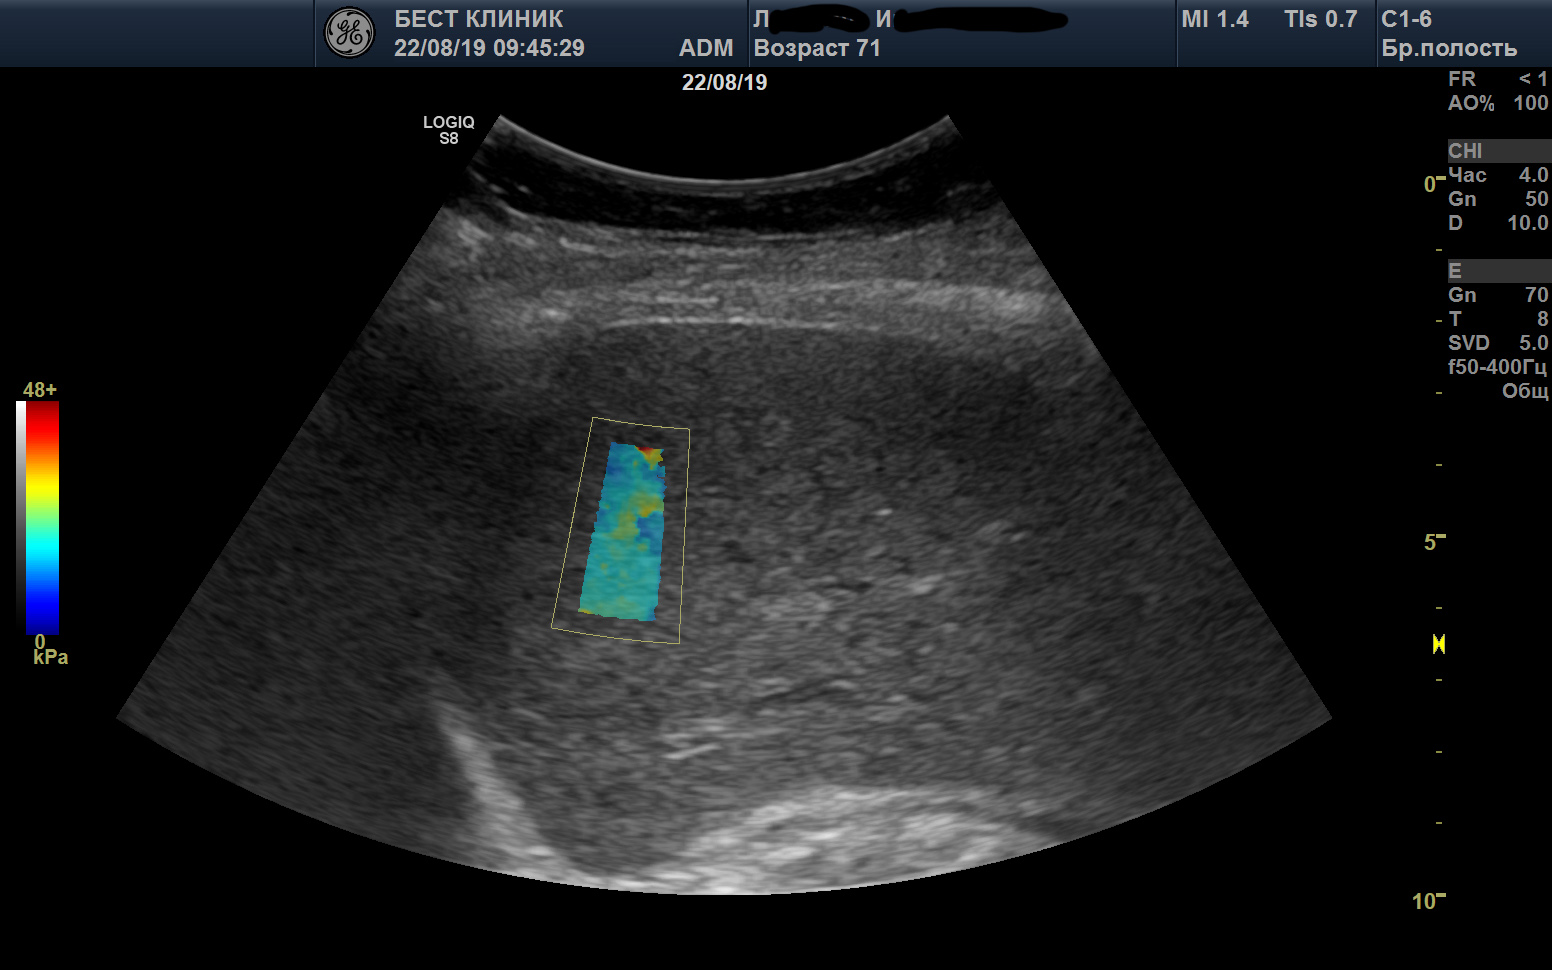

Эластометрия брюшной полости – это современный метод диагностики, который позволяет оценить состояние тканей органов в брюшной полости с помощью ультразвуковых волн. Это исследование помогает выявить различные заболевания на ранних стадиях, таких как цирроз печени, фиброз, воспалительные процессы и другие патологии, что способствует своевременному назначению эффективного лечения.

УЗИ органов брюшной полости, хорошая визуализация. Ну как тут не поизучать сегменты печени:)

УЗИ органов брюшной полости и эластография печени на Mindray Resona i9